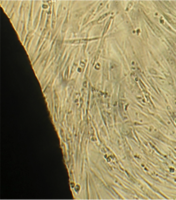

Монослой оставался целостностным и равномерным на всей поверхности чашки Петри, клетки вблизи образца сохраняли характерное для культуры фибробластов взаимное расположение и направление роста (рис. 39).

Морфология их также соответствовала сроку роста: клетки веретеновидной формы с гомогенной цитоплазмой и центрально расположенным пузырьковидным ядром неплотно прилежали друг к другу и анастомозировали своими отростками.

В последующие сроки мы также не наблюдали каких-либо морфологических признаков воздействия имплантата на культуру фибробластов.

Клетки формировали равномерный монослой, плотность которого соответствовала сроку роста культуры после пассирования и не зависела от расстояния до образца (таб. 17).